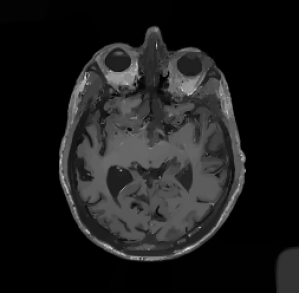

In multi-modality imaging one is often in possession of a specific piece of prior knowledge, namely a side information v𝑣v which is known to have some “common structure” with the true solution u𝑢u of the inverse problem [4]. The literature on this topic is rich with some works as early as the 1990’s so we only list a couple of key papers here. For instance, v𝑣v could be a high-resolution photograph which assists the reconstruction of low-resolution hyperspectral images [5, 6, 7, 8, 9] or an anatomical (MRI or CT) image for the reconstruction of PET images [10, 11, 12, 13, 14, 15, 16, 17], see Figure 2. This strategy has also been used for functional MRI (fMRI) [18], spectral CT [19], electrical impedance tomography (EIT) [20] and multi-contrast MRI [21, 22, 23, 24, 25, 26].

Figure 1: In many applications two images of different contrast and resolution are acquired. Images courtesy of D. Coomes, P. Markiewicz and J. Schott.